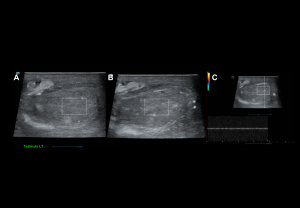

Comprehensive evaluation includes grey-scale, colour, power, and spectral Doppler of the testes, epididymides, and scrotal contents.

Technique:

- Patient positioning: Supine, hips and knees flexed in external rotation; scrotum elevated on a folded towel; penis draped against the lower abdomen.

- Equipment: High-frequency linear transducer (7–14 MHz).

- Scanning planes: Longitudinal and transverse images of each testis; comparative transverse view at the midline for simultaneous evaluation.

- Parameters: Morphology, size, echogenicity, and vascular flow.

Initial assessment: Examine scrotal skin for symmetry, thickening, or edema. Start with the asymptomatic testis to optimize Doppler and compare findings with the contralateral side.